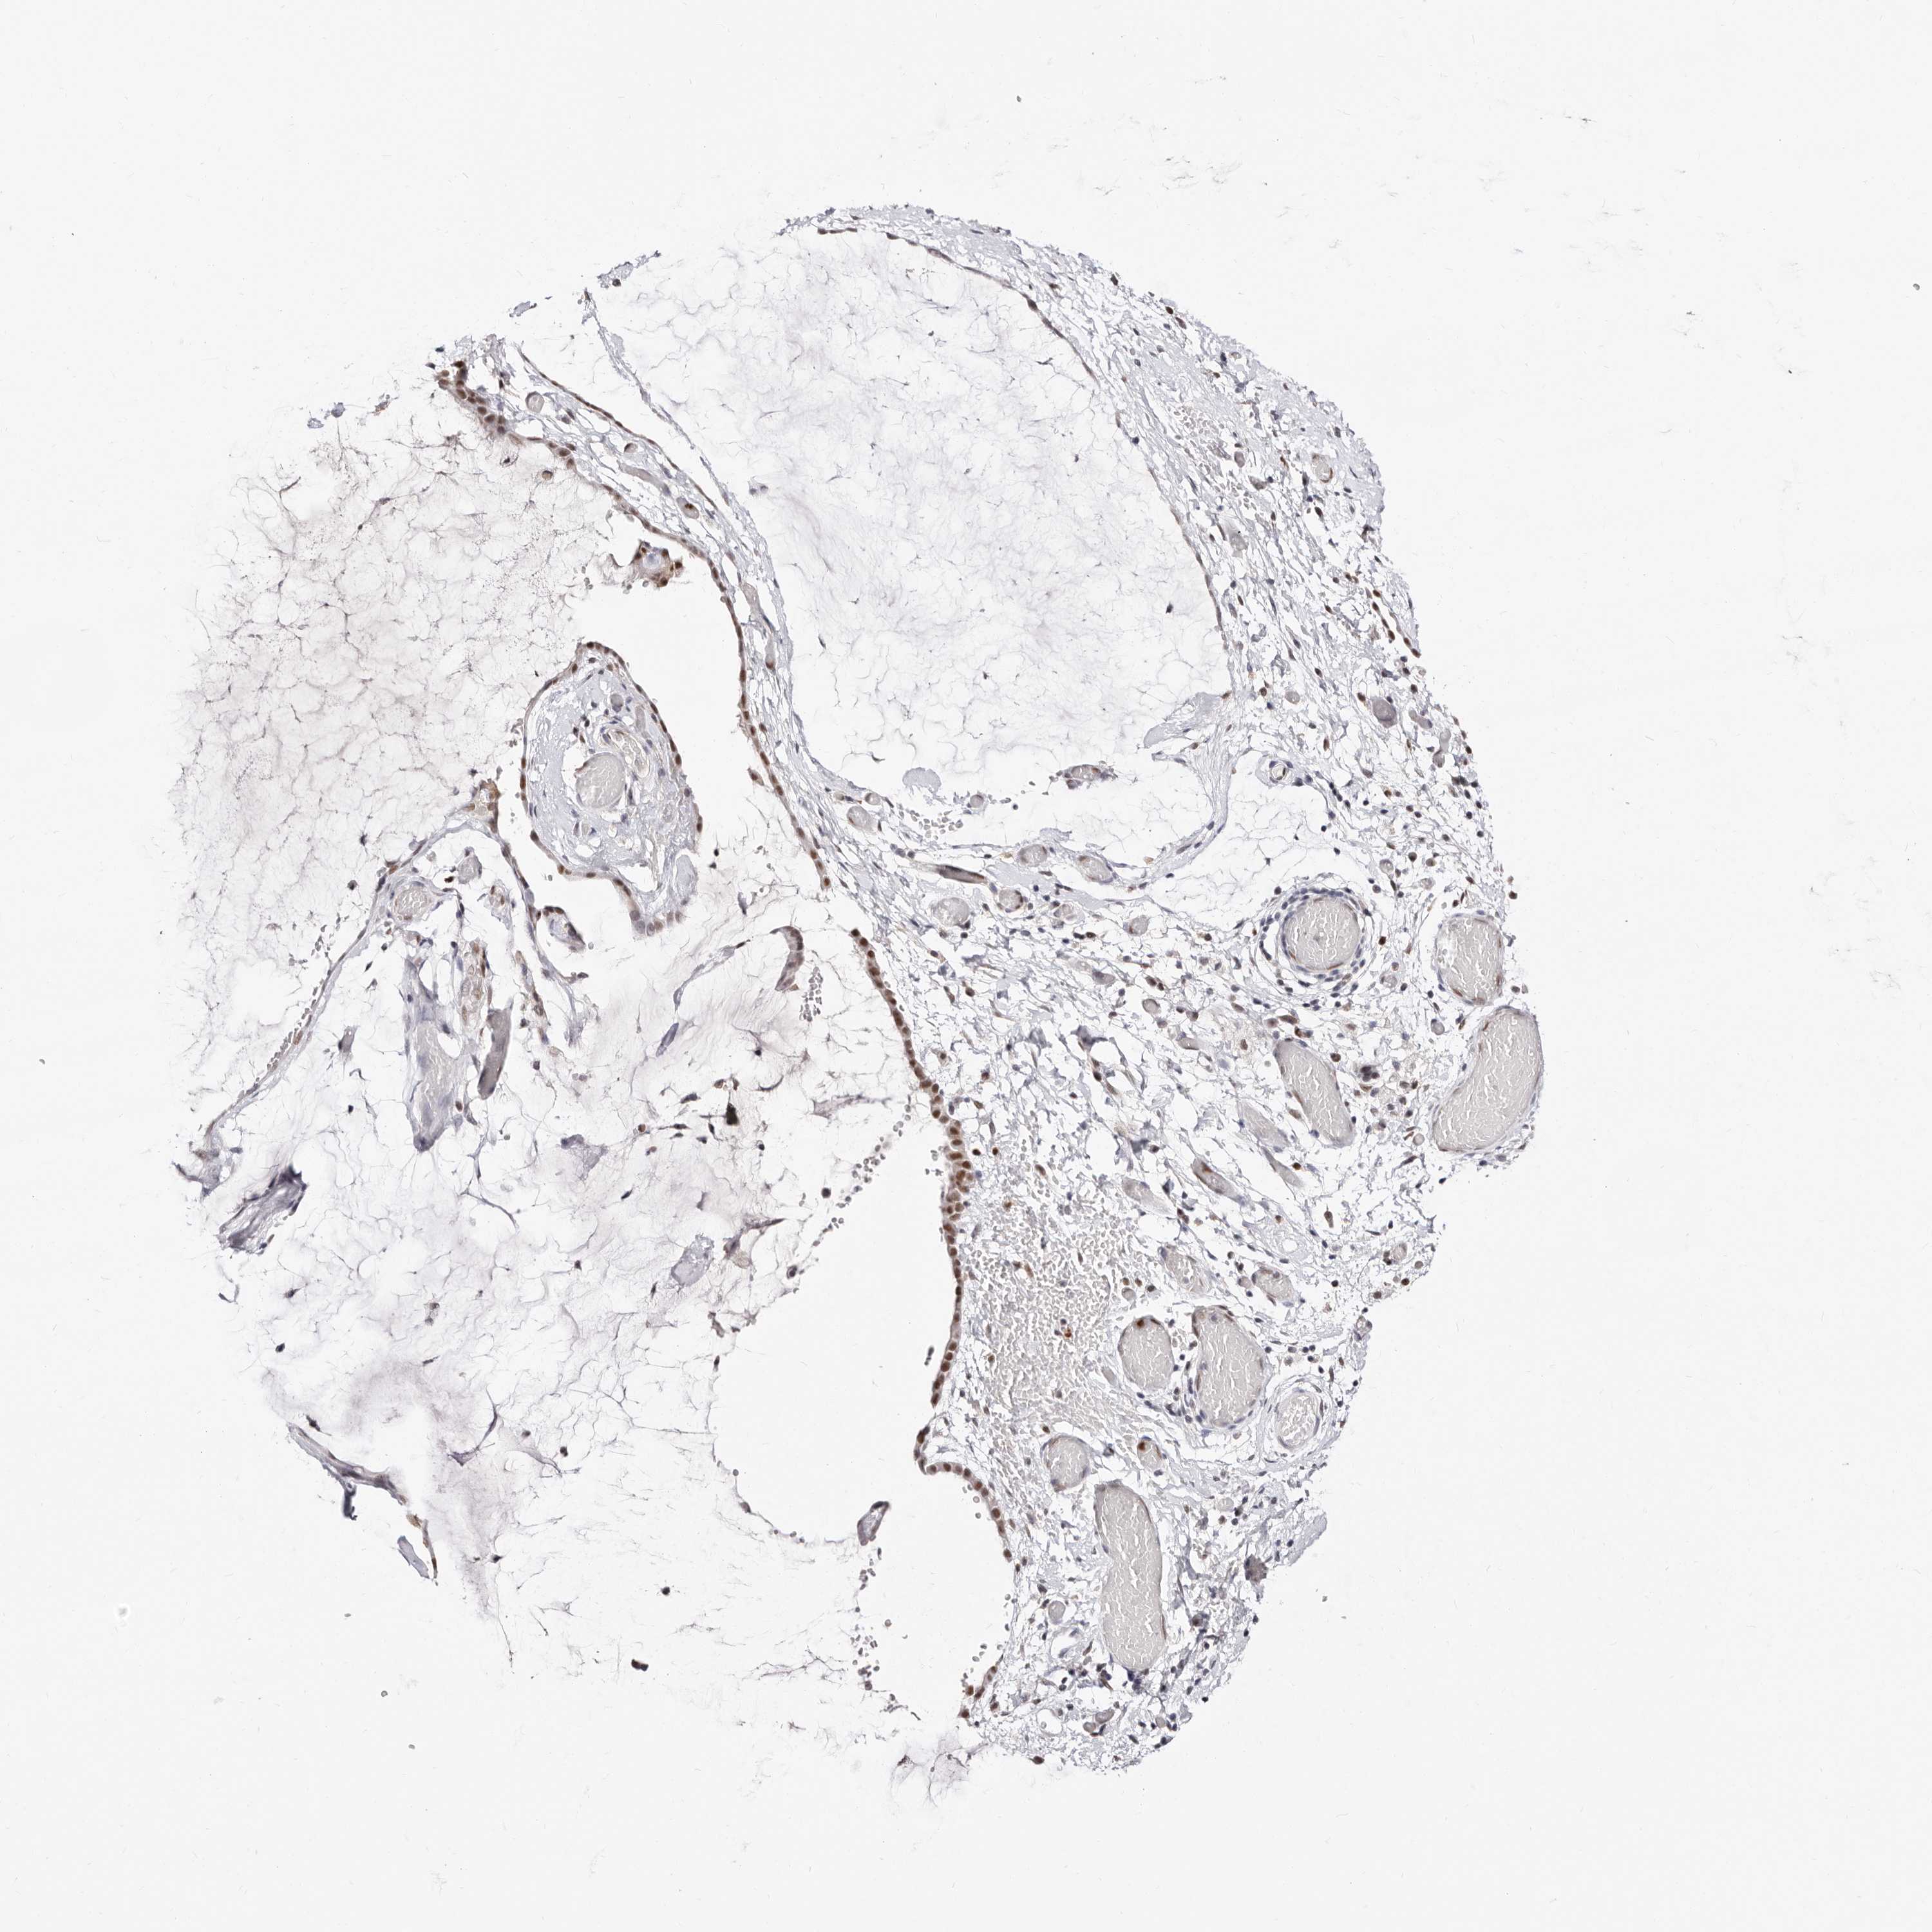

OVARIAN CANCER - Protein expressioni

A mouse-over function shows sample information and annotation data. Click on an image to view it in a full screen mode. Samples can be filtered based on level of antibody staining by selecting one or several of the following categories: high, medium, low and not detected. The assay and annotation is described here.

Note that samples used for immunohistochemistry by the Human Protein Atlas do not correspond to samples in the TCGA dataset.

Antibody stainingi

Antibody staining in the annotated cell types in the current human tissue is reported as not detected, low, medium, or high, based on conventional immunohistochemistry profiling in selected tissues. This score is based on the combination of the staining intensity and fraction of stained cells.

Each image is clickable and will lead to virtual microscopy that enables deeper exploration of all samples and also displays staining intensity scores, fraction scores and subcellular localization as well as patient and tissue information for each sample.

Antibody HPA029480

Antibody HPA029481

Cystadenocarcinoma, serous, NOS

Carcinoma, endometroid

Cystadenocarcinoma, mucinous, NOS

Carcinoma, NOS